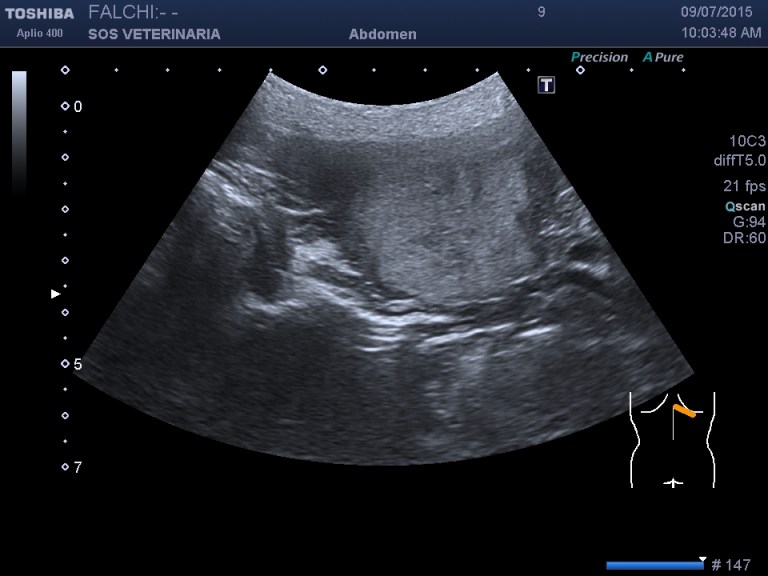

controllo dopo 4 mesi

la lesione e’ cresciuta, il cane sotto somministrazione di vetoryl e’ migliorato nei sintomi dell’ipercorticosurrenalismo ,bene sul piano generale viene visto solo per un controllo

- Nessuna informazione diversa per quello che riguarda l’esame ecografico del fegato e la presa del contrasto si confermano le lesioni individuate e l’ipoenanchement in fase portale.